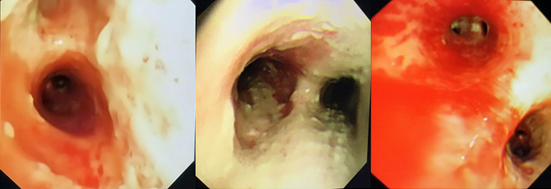

气管镜表现(2018年1月15日):气道狭窄,黏膜明显充血水肿,表面大量白苔,触之易出血。

图片

IAA患者气管镜下典型表现是气道黏膜明显充血水肿,气道黏膜表面白色假膜附着,气道狭窄及痉挛比较明显。

气管镜检查的重要意义在于:①观察气道病变特点和范围;②有助于获取高质量的下呼吸道标本,提高真菌培养阳性率;③获得BALF,以辅助早期诊断(BALF GM试验等);④由于IAA患者气道黏膜病变严重,气道明显狭窄,所以患者大多存在严重的痰液引流不畅问题,通过气管镜下吸痰,可以加强痰液引流,能够在一定程度上改善患者预后;⑤可以通过气管镜进行气道内给药。

来自欧洲7个国家、美国和台湾的29名专家就IAA的诊断标准发布了专家共识,并于2020年发表在Intensive Care Medicine杂志上,他们将IAA明确分为两型,即曲霉菌性气管支气管炎和侵袭性肺曲霉菌病,这一标准也高度强调了气管镜的重要性。无论是气管镜镜下的表现,还是气管镜获取的BALF标本进行GM试验或曲霉培养,均是诊断标准中非常重要的条目。